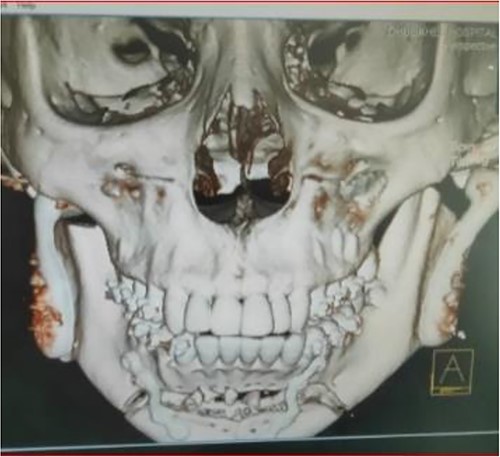

The clinical examination of the patient revealed a bird face deformity, chin deviated to the right side, restricted mouth opening of about 5 mm (Fig. 2), class II malocclusion on the right side and class I malocclusion on the left side with protruding upper anterior teeth and an open anterior bite. Cone-beam computed tomography images showed left-sided bony ankylosis of the temporomandibular joint (Fig. 3). Since the patient is skeletally mature, mandibular growth is ceased, and there is recurrent TMJA, reconstruction with an artificial prosthesis can be used as an alternative option [9, 10]. In this case, resection of the left-sided ankylotic bony mass with reshaping of the remaining bilateral ramus and temporal bone was performed for fitting and fixation of a custom made temporomandibular joint prosthesis of Lyka Smith (Fig. 7), Williams Landing, Australia, followed by advancement genioplasty (Figs 8 and 9) [10].

Preoperative computed tomography (coronal section): left-sided TMJA with radiographic suggestion of previous condylectomy at right-sided temporomandibular joint.